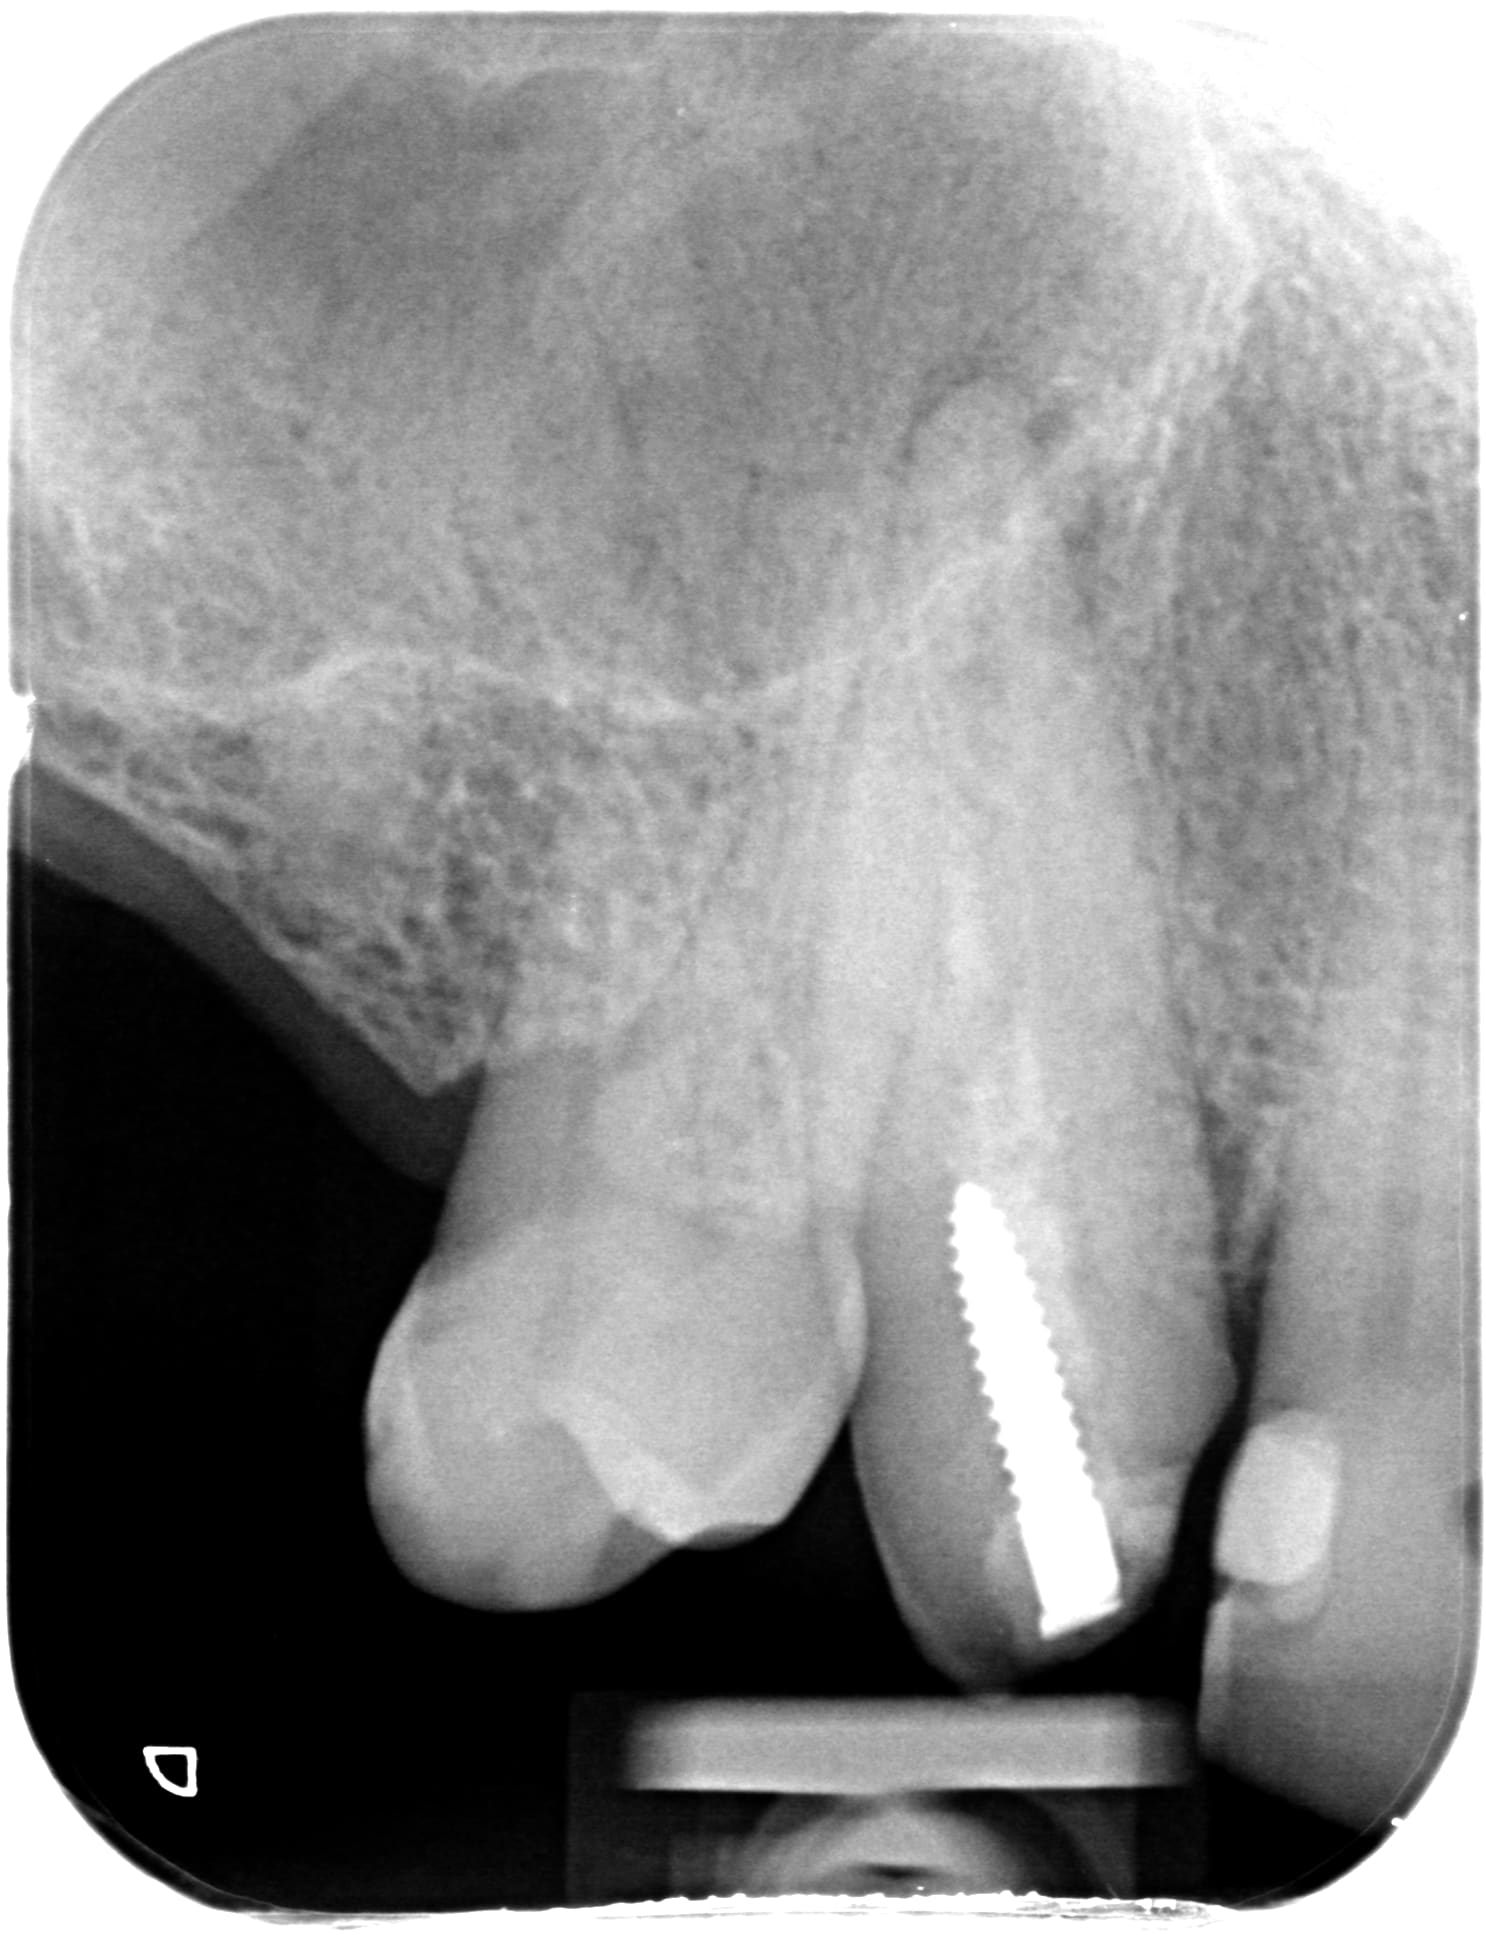

La par exemple, même a 410e la coiffe ceram mon confrère a été rentable.

Nouveau patient, motif: couronne descellée sur 13.

heureusement qu'il reste un peu de NPC pour refaire ;)

jusqu'a quand ???

En cadeau bonus... la 26 d'une jeune de 30 ans.

Meme a 250e la coiffe tu gagnes du pognon... 2 RDV de 10 min.